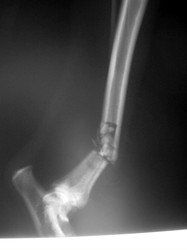

Fijación Externa

PRÁCTICAS CURSO DE FIJACIÓN EXTERNA PERFECCIONAMIENTO.

Híbrido.